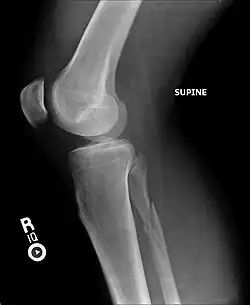

Fracture of the medial malleolus seen on X-ray scan (left ankle)

Common symptoms of a Maisonneuve fracture are pain, swelling, tenderness, and bruising around the ankle joint and inferior (or distal) tibiofibular joint. More specifically, as a pronation-external rotation injury, pain during external rotation of the ankle joint is expected. Additionally, there is a reduced range of motion of the foot and an inability to weight-bear due to ankle pain.[4][7] Pain may also be felt around the medial and lateral aspects of the ankle, and more rarely around the superior (or proximal) tibiofibular joint.[9] Damage to the deltoid ligament or interosseous membrane can cause haemorrhaging around the surrounding tissues, resulting in a localised oedema.[8]

Fracture of the lateral malleolus seen on X-ray scan (left ankle)

The Maisonneuve fracture generally follows a specific pattern of injury. The following are described as subsequent events that result in a Maisonneuve fracture:[3][4][12]

• Forceful, external rotation of the ankle joint results in the tearing of the deep deltoid ligament and/or an avulsion fracture of the medial malleolus.

• The ankle mortise is subjected to excessive torque, rupturing the syndesmotic ligaments and anteromedial ankle joint capsule.

• Rotative energy is transferred upwards along the interosseous membrane, damaging it in the process.

• The force results in a spiral, sometimes an oblique, fracture at the neck of the proximal fibula.

In cases where the anterior aspect of the tibiofibular syndesmosis can resist mechanical stress, only an oblique fracture of the lateral malleolus is produced. Diastasis of the lateral malleolus may also occur, in which it is posterolaterally displaced from the tibia.[9]